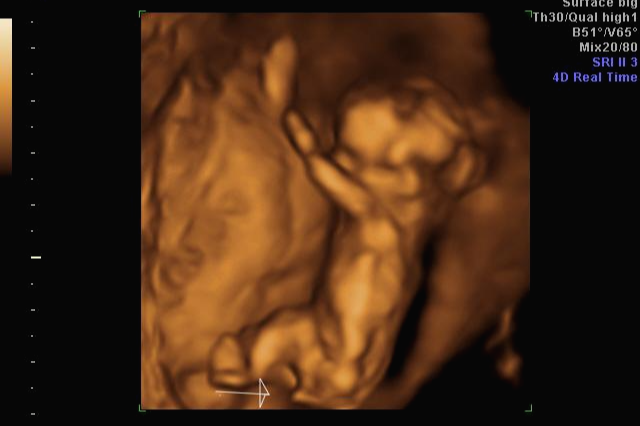

30주 차! 다행히? 다시 성별반전은 없는 것 같아요~ 허벅지 뼈? 길이 봐주시면서 스쳐갔는데 다리사이에 아무것도 보이지 않네요~

입체 초음파 사진은 항상 만족스러워요! 사진 보면 벌써 태어난 아기처럼 어찌 이리 이목구비 뚜렷하고 아이 얼굴이 선명하게 잘 보이는지~ 제아이라 이렇게 사랑스러운 걸까요~? ㅋㅋㅋ

아무튼 저에게 성별반전이 있었지만 아이가 건강한 것만으로도 너무 행복해요~ 이제 출산까지 2달 남았는데 지금처럼만 건강하게 자라다오~~~